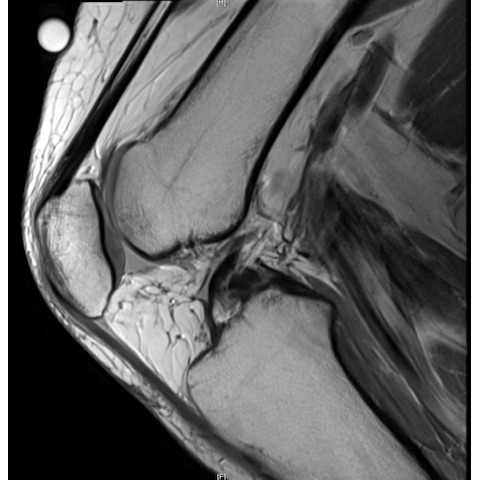

| The Case Of The Unextendable Knee - Page #3 | |||